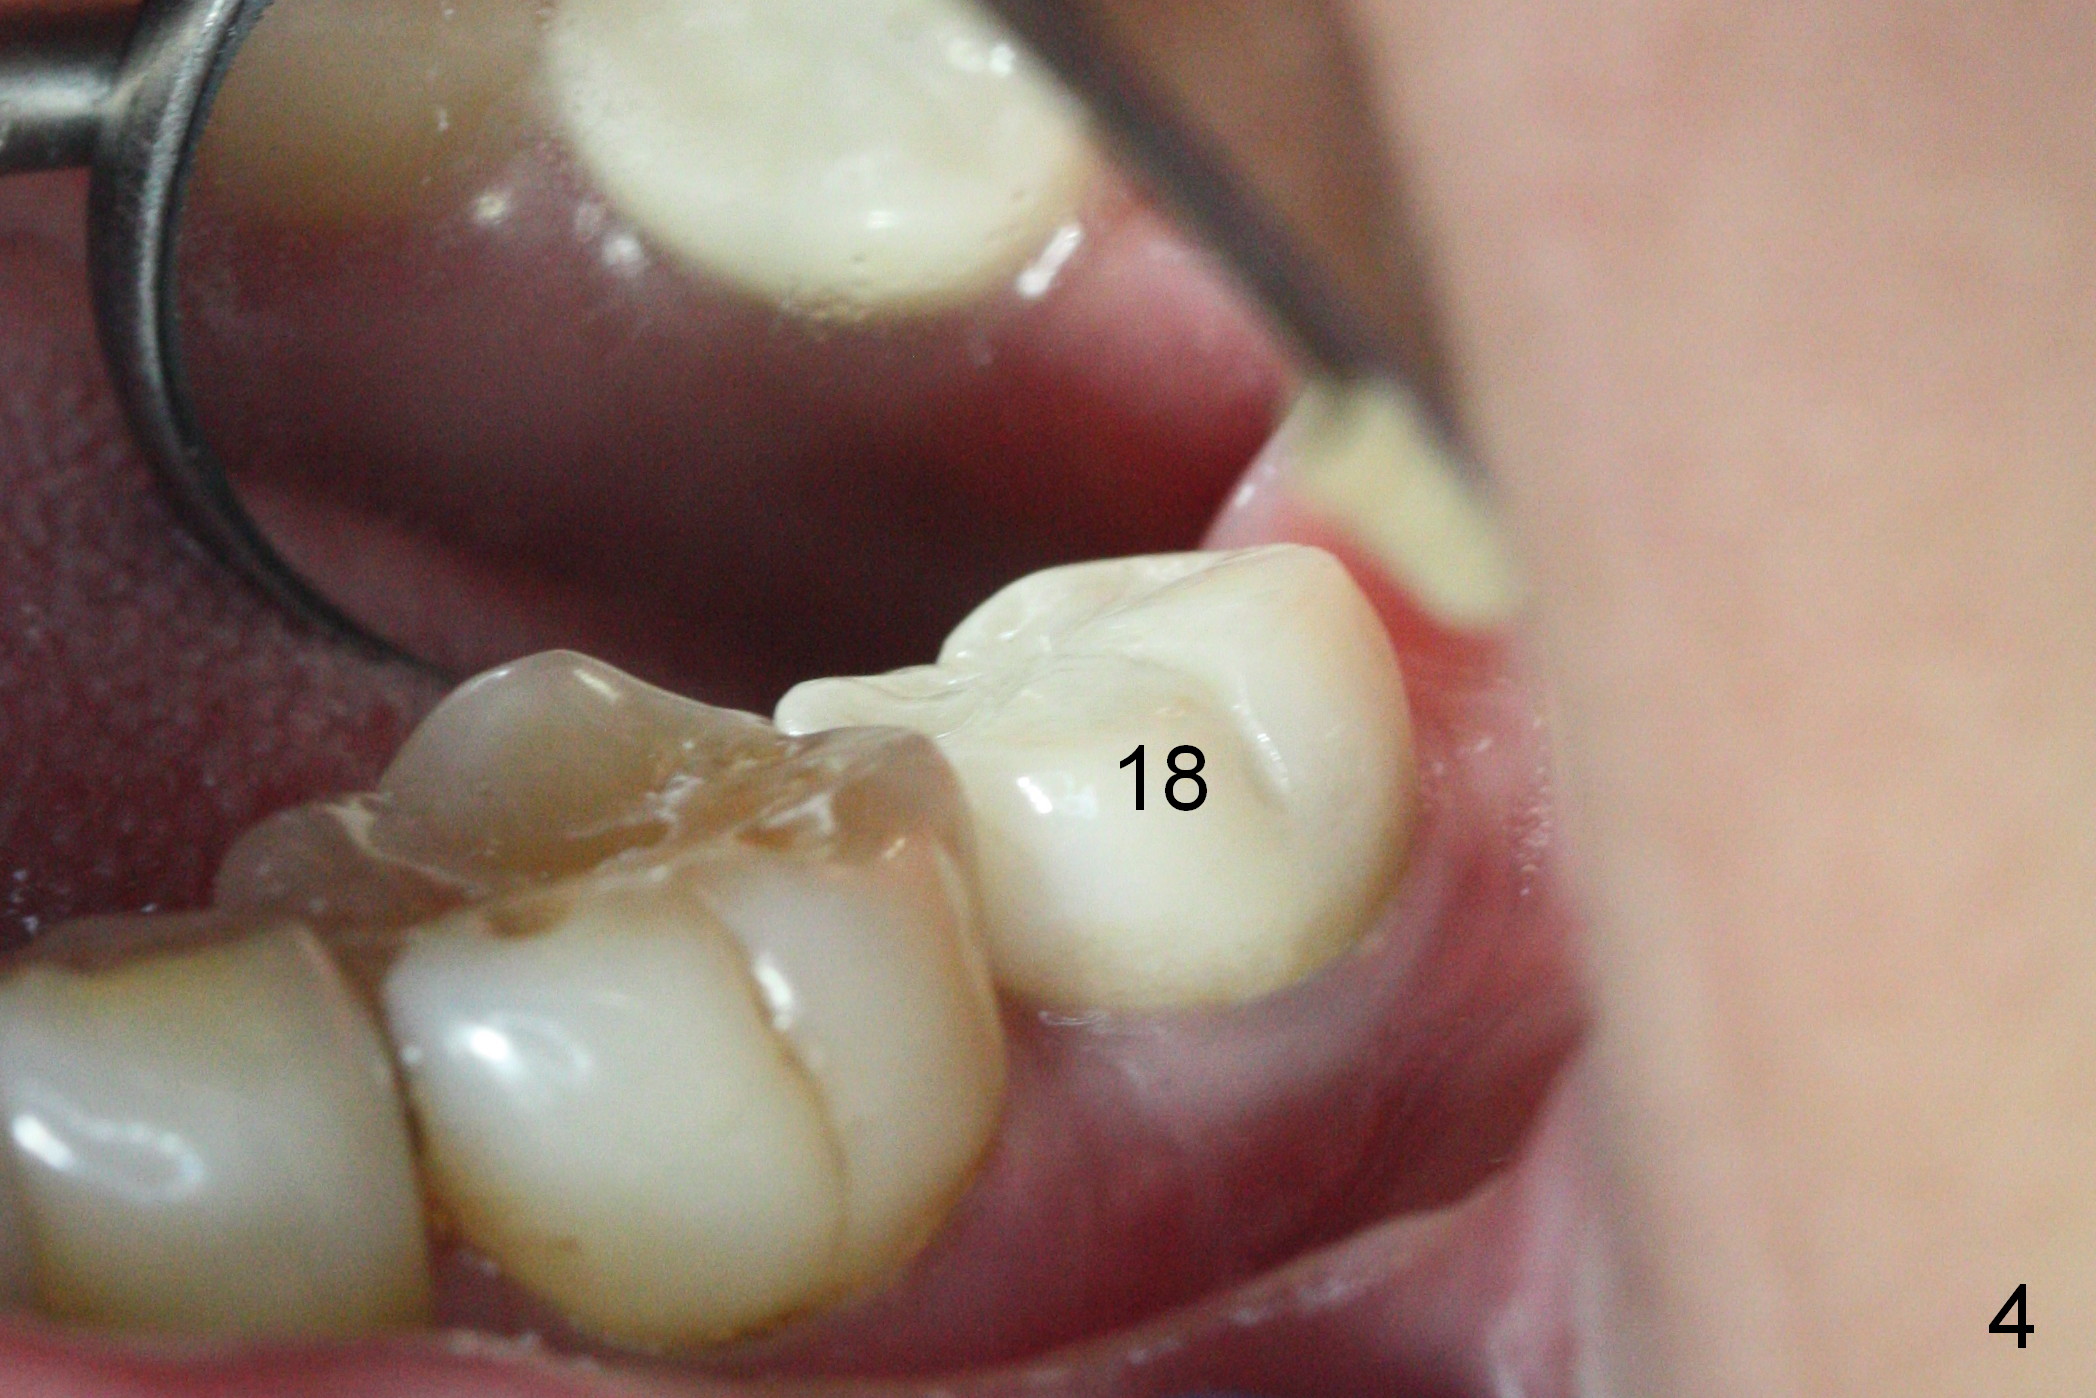

Clinically the existing crown is a little too small (Fig.4). Since the implant is not too small (5 mm in diameter) and has been placed 3 years 4 months, the implant must be well osteointegrated (take PA and BW). The crown should be as wide as possible buccolingually with the wide buccolingual contact.